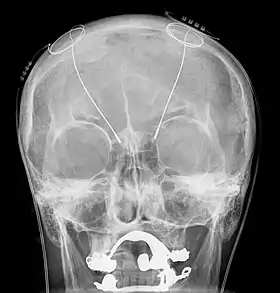

DBS-probes shown in X-ray of the skull (white areas around maxilla and mandible represent metal dentures and are unrelated to DBS devices)